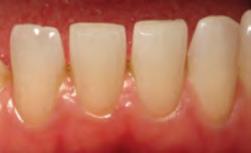

1. Well-healed tissue 2 weeks post-op.

Note: Perfect sulcular fluid control is mandatory if bonding and luting is adjacent to gingival sulcus.1